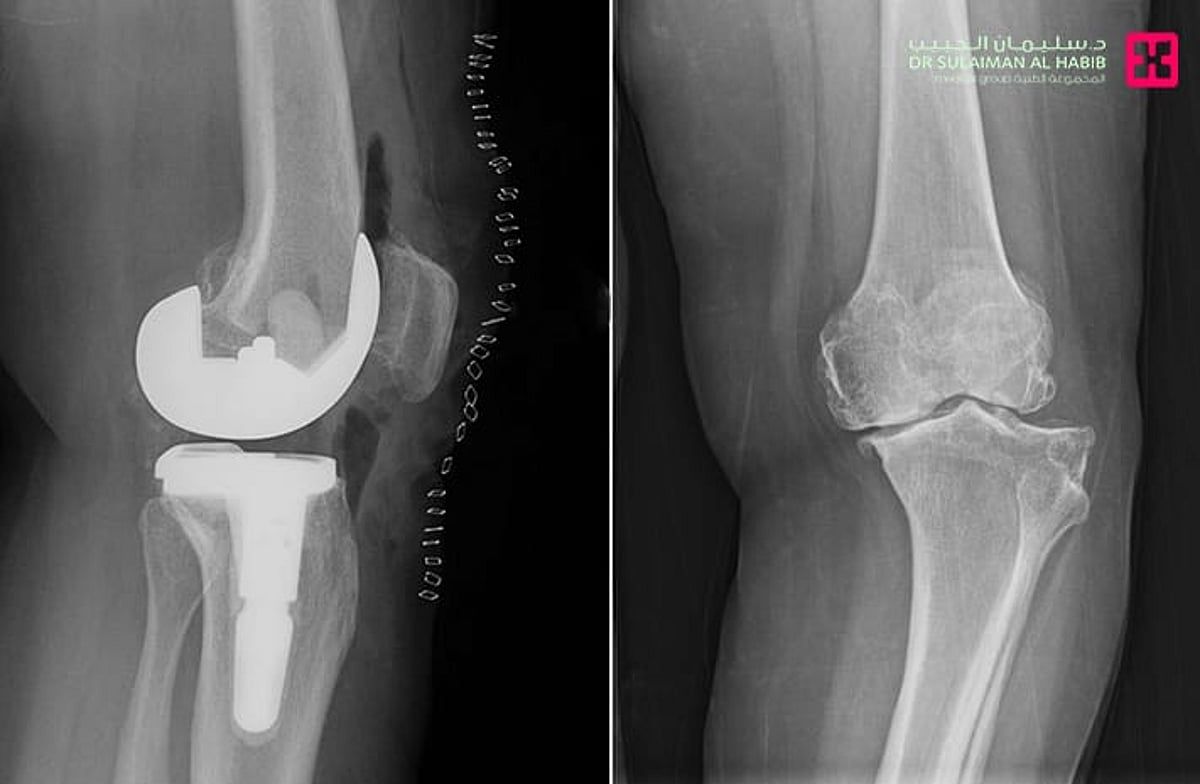

نجح مستشفى الدكتور سليمان الحبيب بالقصيم في إجراء عملية نوعية ناجحة لاستبدال مفصل الركبة اليسرى بتقنية حديثة تُخفّف الآلام وتُسرّع التعافي، منهيةً معاناة سيدة ستينية كانت تعاني من خشونة شديدة واحتكاك حاد وتلف في غضاريف المفصل.

وأوضح الدكتور عبدالله الشهراني، استشاري جراحة العظام واستبدال المفاصل الصناعية ورئيس الفريق الطبي المعالج، أن المريضة حضرت وهي تشكو من آلام وتورم وتغيّر في شكل الركبة وصعوبة في الحركة. وأضاف أن الفحص السريري والفحوصات الدقيقة أظهرت وجود احتكاك حاد وتآكل في عظمتي المفصل، إضافة إلى ارتخاء شديد في الأربطة الجانبية وخلل في حركة عظمة رأس الركبة.

وبيّن الشهراني أن الفريق الطبي درس الحالة بدقة، وتوصّل إلى أن استبدال المفصل بآخر صناعي هو الخيار الأنسب، حيث أُجريت العملية باستخدام مفصل خاص بهذه الحالات وبالاستعانة بأحدث الأجهزة الطبية. واستغرقت العملية نحو 60 دقيقة، وتكللت بالنجاح، إذ تمكّنت المريضة من المشي بعد ساعات فقط من إجرائها، وغادرت المستشفى بعد أيام بحالة صحية جيدة.